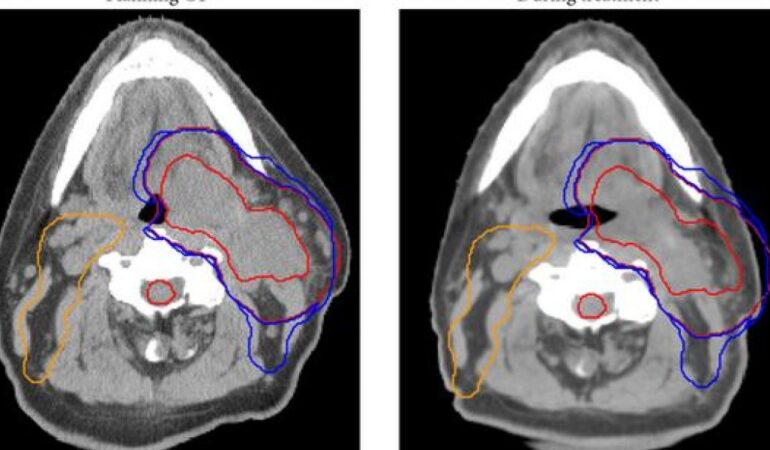

Tedavi süreci ilerledikçe, belirli aralıklarla yapılan görüntüleme ve klinik değerlendirmeler sayesinde hastanın anatomik yapısında veya hedeflenen alanda meydana gelen değişimler izlenir. Bu değerlendirmeler sonucunda, gerekli görülen durumlarda mevcut tedavi planı yeniden ele alınabilir ve güncellenebilir.

IMRT ve adaptif planlama, birlikte ele alındığında tedavi sürecinin daha esnek biçimde değerlendirilmesine olanak tanır. Tedavi süreci boyunca hastanın anatomik yapısında veya hedeflenen alanda meydana gelebilecek değişimler, adaptif planlama yaklaşımıyla göz önünde bulundurulabilir. Bu sayede başlangıçta oluşturulan IMRT planı, klinik gereklilikler doğrultusunda yeniden değerlendirilerek güncellenebilir.

Gelişmiş görüntüleme sistemleri, adaptif radyoterapinin temel bileşenleri arasında yer alır. Tedavi öncesi ve sırasında kullanılan bu sistemler, hedef alanın ve çevre dokuların güncel durumunun değerlendirilmesine katkı sağlar.

Bu görüntüleme verileri, adaptif planlama sürecinde mevcut tedavi planının gözden geçirilmesine yardımcı olur. Böylece radyoterapi süreci, hastaya ait güncel klinik veriler doğrultusunda ele alınabilir.